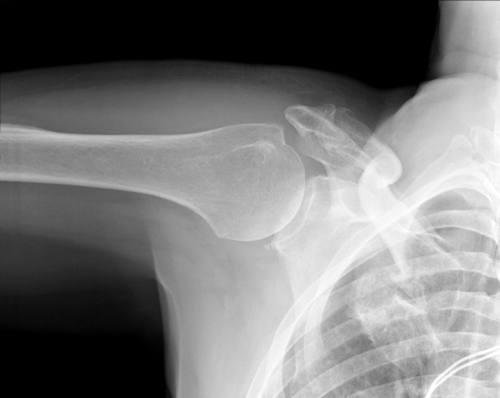

Brutet nyckelben (nyckelbensfraktur)

Ett brutet nyckelben (nyckelbensfraktur) är ett vanligt benbrott. Det förekommer oftare hos barn och ungdomar, över hälften av frakturerna drabbar barn under tolv år.

Många nyckelbensfrakturer är den typ av brott som kallas för “greenstick”. I dessa fall bryts inte nyckelbenet av, det böjs istället lite grann  ungefär som när man försöker böja en tunn gren på ett träd. Greenstickfrakturer drabbar oftast barn under tolv år.

Behandlingen av ett brutet nyckelben beror på hur frakturen ser ut. I många fall kan en läkare fastställa att det handlar om en nyckelbensfraktur genom att undersöka och ställa frågor. Vissa arm- och axelrörelser leder till smärtor och det är även vanligt att den skadade håller armen nära kroppen för att få mindre ont. Nyckelbensfrakturer brukar röntgas så att skadans omfattning kan bedömas.